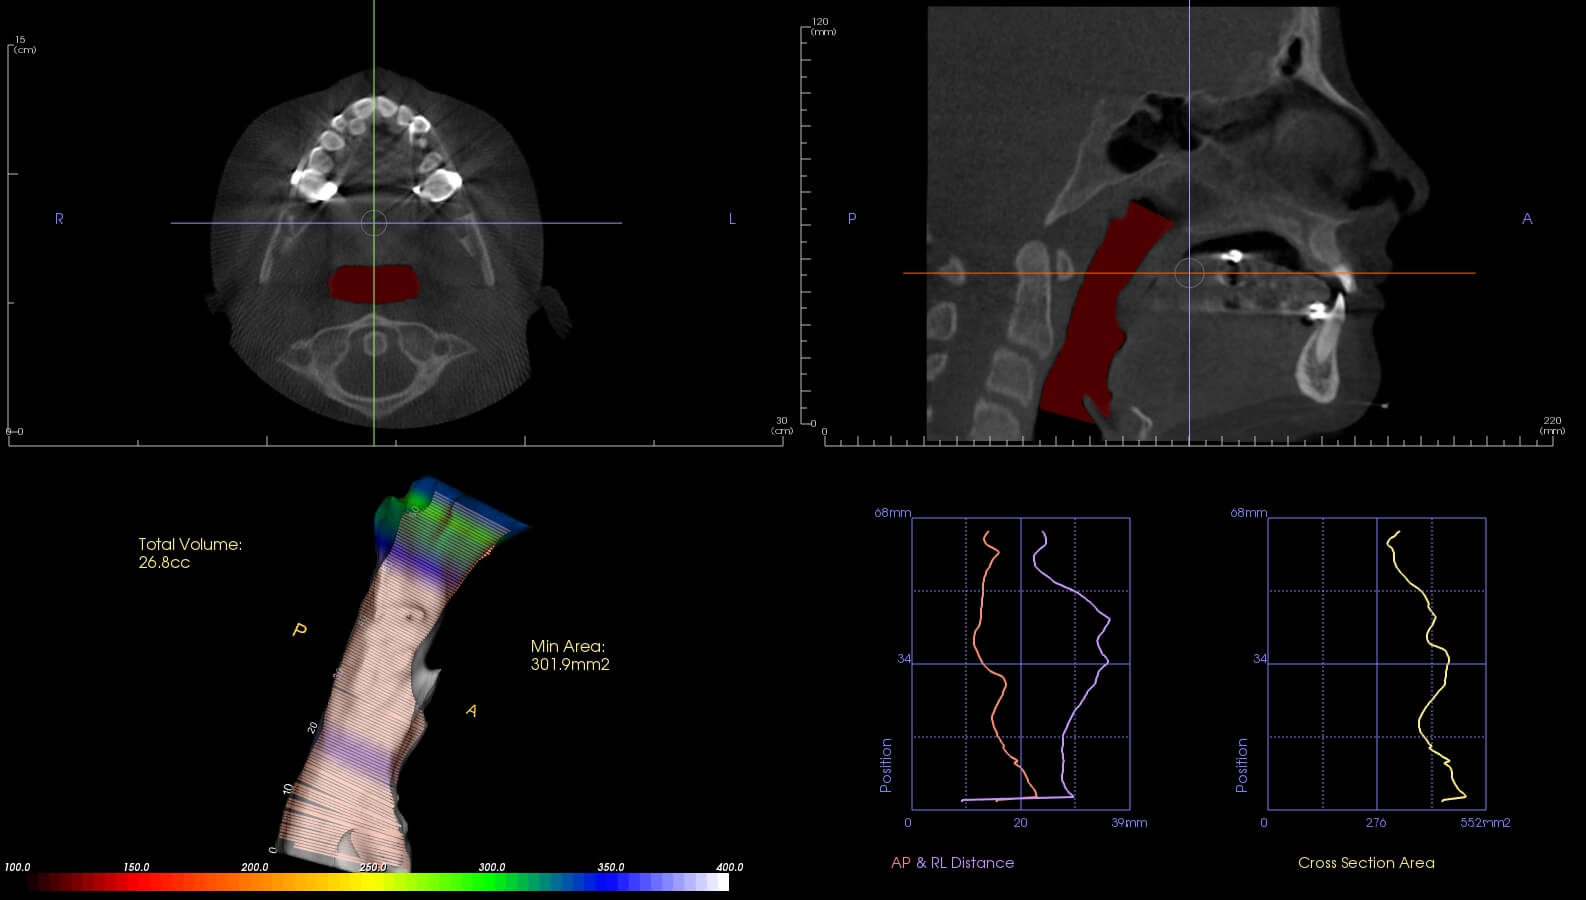

These are before and after CBCT images of patients treated at Marlo A. Miller, DDS. Both struggled with enlarged adenoids and tonsils. An adenotonsillectomy, or removal of the tonsils, was performed based on Dr. Miller and an ENT recommendation. This procedure alleviates airway restriction contributing to breathing/sleep issues and reduced overall health and wellness. Dr. Miller also did some minor Upper and Lower expansion. There is a Significant airway change in both patients, and both report sleeping better and feeling better overall.